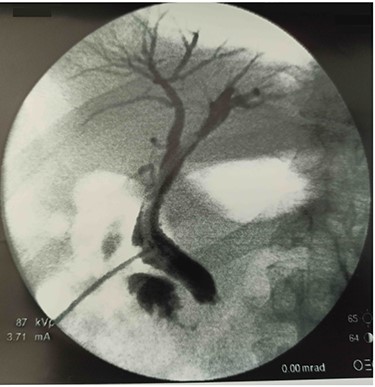

After 40 days, patient had no signs of liver and biliary complications and kehr’s tube appeared normally placed. Blood count and bilirubin was normal with alkaline phosphatase 447 U/l, AST 112 U/l, ALT 162 U/l. Trans-kehr cholangiography showed normal size of CBD (Fig. 3), so it was removed and replaced with a single plastic biliary stent (9-cm length and 10-Fr diameter) through an ERCP.